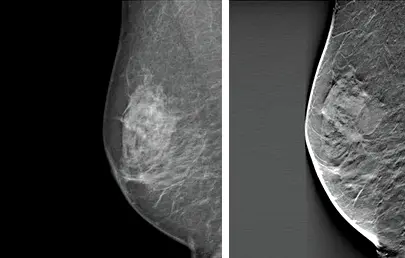

A Three-dimensional (3D) mammogram, also known as breast tomosynthesis, is a type of digital mammography in which x-ray machines are used to take many pictures of thin slices of the breast to produce a 3D image. This process is similar to how a computed tomography (CT) scanner produces images of structures inside of the body.

- With a mammogram, glandular and fibrous tissue is white and fat is seen as black.

- Cancers are also seen as white so they can hide in normal glandular breast tissue, particularly if the breasts are dense which is seen in our clinic population.

- The 3D tomosynthesis takes images through the breast while the mammogram is taken, and the computer reconstructs this into 1mm slices through the breast.

- Our specialist radiologist reads this in conjunction with the state of the art 2D digital images.

Cancer visible on the right 3D mammogram but not the left 2D mammogram.